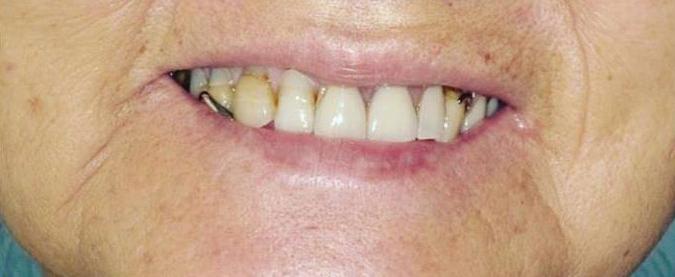

Submitted By Sivakumar Sreenivasan, DMD, MDS Dental Implant Center of Rockville

Tooth loss is extremely common among adults, especially as we age. Rather than living with the discomfort and hassles of dentures, many people are opting for what is called “all-onfour” dental implant restoration.

An implant is a small titanium

screw that fits inside your jawbone and replaces the root-part of a missing tooth. Minor surgery is required to insert the implants. Once the implant is in place, a crown is attached to give you a highly realistic-looking and functional prosthetic tooth.

You do not need a dental implant for each and every one of your missing teeth. All you need is four precisely placed implants on the top of your mouth, and four on the bottom, to restore your full smile. That’s the beauty of the all-on-four. And because the implant is made of titanium, it has the unique ability to fuse to living bone and function as part of it. So eventually, the dental implant becomes part of the jawbone and serves as a strong, longlasting foundation for your new teeth.

Besides ensuring that your implants are permanently fixed in place, this bone fusion has another important benefit: it prevents future bone loss in the jaw. This helps to maintain a more youthful facial structure – and better